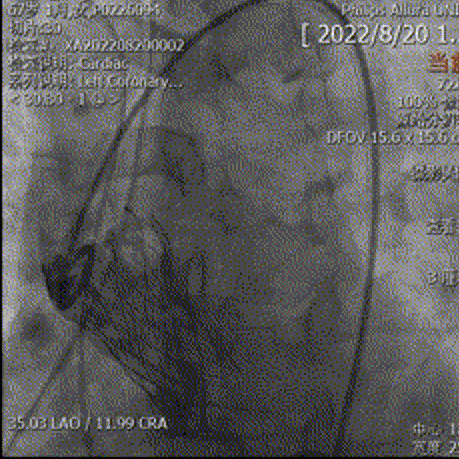

预装TaurusEliteAV23瓣膜,输送系统顺利过弓、跨瓣,于瓣环平面0mm定位释放。

瓣膜过弓跨瓣

瓣膜定位

释放到工作位后瓣膜流入端压缩明显,位置良好,冠脉血流灌注正常,脱钩释放后瓣膜位置良好,形态欠佳。

工作位造影

脱钩后造影

考虑冠脉阻挡风险较高,予以18mm球囊后扩,最终瓣膜形态、位置良好,冠脉血流灌注正常,弓部造影未见异常。

球囊后扩

最终造影